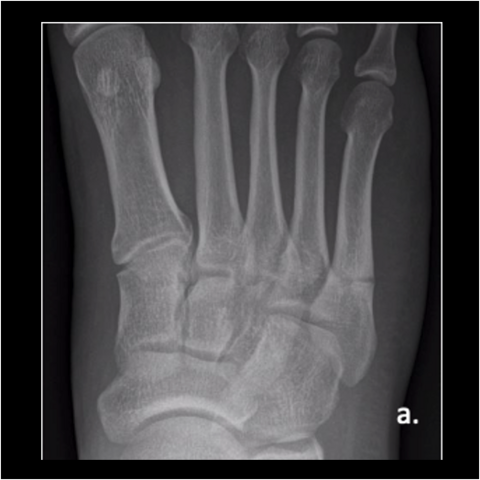

Figure 3a

Figure 3a. A 28-year-old Army officer injured during combatives was able to walk 2 days post-surgery. He started wearing his Army boots 2 weeks after surgery and completed Sapper School 10 weeks after surgery. He then went to Special Forces training within 6 months postop. The patient never had any pain after surgery. Here is the foot when the patient got injured.